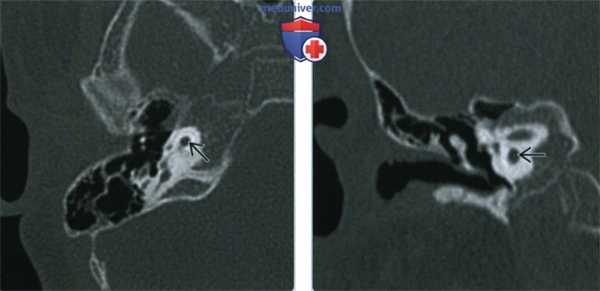

Один пациент, по данным КТ височных костей, имел двустороннюю облитерацию лабиринта, включая улитки с двух сторон, с большей выраженностью патологических изменений справа. На МРТ было выявлено уменьшение количества жидкости в улитке справа, слева количество жидкости в улитке соответствовало норме (рис. 1, 2).

Рис. 1. КТ, аксиальная проекция. Облитерация улитки (стрелка).

Рис. 2. МРТ, аксиальная проекция. Справа — полное отсутствие жидкости в улитке (короткая стрелка), слева — частичное (длинная стрелка).

У одного пациента на КТ определялись двусторонняя аномалия внутреннего уха по типу Мондини (рис. 3), двусторонний локальный порок развития цепи слуховых косточек, костная облитерация лабиринта, включая улитку справа. На МРТ внутриулитковая жидкость справа не определялась, слева количество внутриулитковой жидкости было в норме.

Рис. 3. КТ, аксиальная проекция. Аномалия Мондини, состояние после КИ.